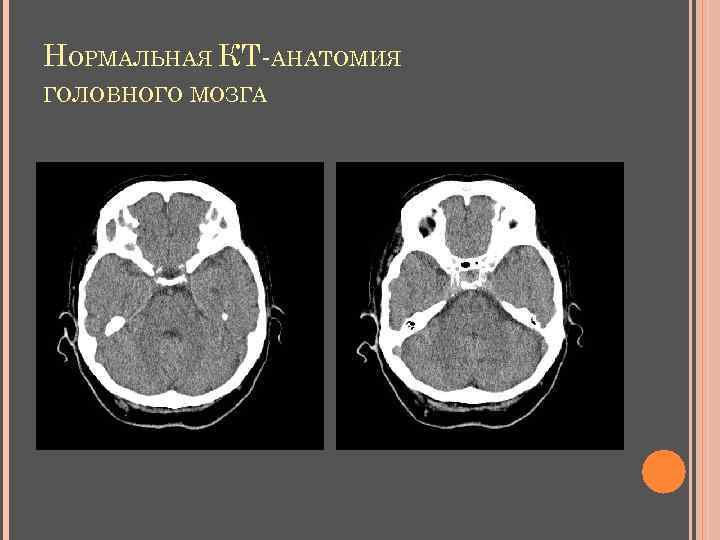

НОРМАЛЬНАЯ КТ-АНАТОМИЯ ГОЛОВНОГО МОЗГА Неизмененные ткани мозга: серое вещество 36 -40 ед. НU, белое вещество 24 -36 ед. НU

НОРМАЛЬНАЯ КТ-АНАТОМИЯ ГОЛОВНОГО МОЗГА